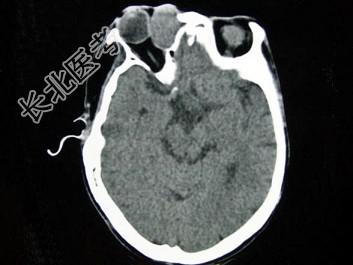

- 单项选择题女,40岁, 右眼反复溢泪伴眼球渐进性突出2年余,眼球运动受限, CT检查如图所示,最可能的诊断是 ( )